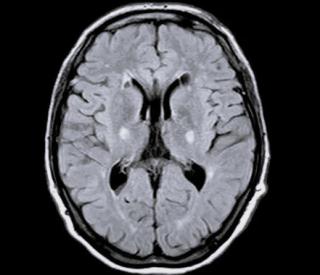

МРТ при атаксии Фридрейха выявляет следующие анатомические аспекты:

На Т1-взвешенных изображениях определяется уменьшение объёма спинного мозга в грудном и шейном отделах, истончение мозжечковых ножек, снижение плотности белого вещества в проводящих путях, возможное расширение борозд в области мозжечка.

На Т2-взвешенных изображениях визуализируется гиперинтенсивный сигнал в спинно-мозжечковых трактах и снижение интенсивности сигнала в области передних и задних столбов спинного мозга.

На Т2-взвешенных изображениях с подавлением жира выявляются зоны дегенерации в области мостомозжечковых трактов, снижение интенсивности сигнала от спинного мозга, возможные признаки атрофии базальных ганглиев и ствола мозга.

На изображениях с подавлением сигнала от воды определяется структурное истончение мозжечковых путей, выраженная атрофия спинного мозга, возможное уменьшение плотности белого вещества в коре больших полушарий при тяжёлом течении заболевания.